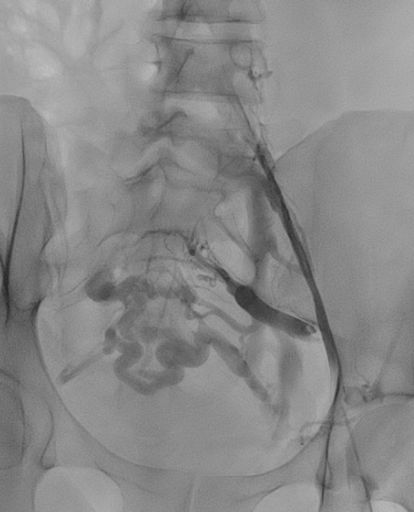

תמונות מהצנתור:

בתמונה 1:

- ונוגרפיה – היצרות של וריד כסל חיצוני ומשותף משמאל, התפתחות מעקפים מורחבים המנקזים באופן איטי את הגף התחתון.

- וריד צר- תכלת

- וריד עוקף מורחב- צהוב

- אזור ההיצרות הקשה – סגול

בתמונה 2:

- ורידים מורחבים "גודש ורידי אגן"